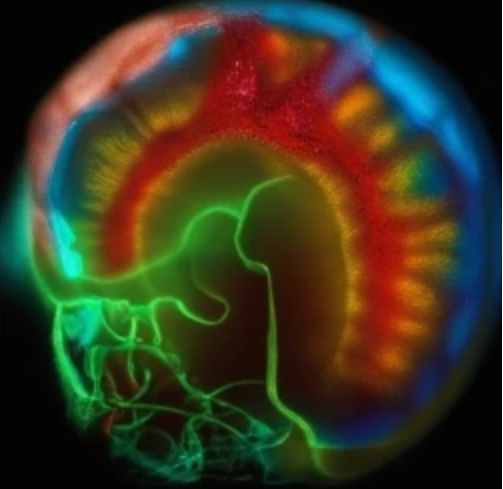

CXC趨化因子受體2(CXCR2)是G蛋白偶聯受體,在哺乳動物的免疫系統中起著重要作用。CXCR2主要在粒細胞和巨噬細胞表達,它可以結合多種C